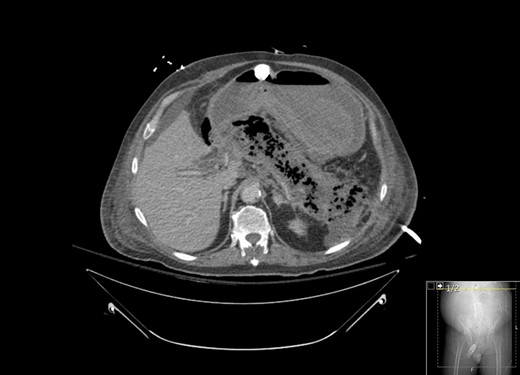

A 67-year-old male presented to his local hospital with postprandial right upper quadrant (RUQ) abdominal pain and vomiting. CT scan of the abdomen and pelvis with oral contrast showed extensive stranding and ill-defined fluid attenuation surrounding his pancreas (Fig. 1). Initial serum amylase and serum lipase levels were 2918 and 17 360, respectively. He was diagnosed with acute, necrotizing, gallstone pancreatitis and developed gastric outlet obstruction (GOO) 9 days after the onset of his symptoms, at which time he was transferred to our institution for further care. On arrival, he had GOO and renal failure (creatinine 2.1 mg/dl). A gastro-jejunal (GJ) feeding tube was placed for jejunal feeds and gastric decompression. On hospital Day 7, the patient’s pain had resolved and a cholecystectomy was attempted laparoscopically, but was converted to open due to inflammation around the infundibulocystic junction. Subsequently, a follow-up contrasted CT showed marked interval necrosis of pancreatic tissue resulting in numerous lobulated soft tissue and gas collections in the upper abdomen, midline upper pelvis, and in the gallbladder fossa (Fig. 2). A pancreatic drain was placed by interventional radiology (IR) on hospital Day 20 for interval increase in pancreatic necrosis on CT. On hospital Day 23, IR embolization of gastroduodenal artery (GDA) was performed due to GI bleeding. Laparoscopic necrosectomy with malencot drain placement was performed on hospital Day 36. Post-operatively, he had a large upper GI bleed requiring emergent endotracheal intubation and initiation of the massive transfusion protocol. Angiography was performed and was negative. On the following day, hospital Day 39, GI performed an EGD and found hemorrhagic gastritis, but no localizable bleeding. He was placed on high dose PPI, carafate and octreotide. He progressed to acute renal failure with initiation of hemodialysis on hospital Day 45. On hospital Day 47, a follow-up EGD was done with exchange of the gastrojejunostomy tube, and hemorrhagic gastritis was still present. He was transferred to the general surgery inpatient unit the following day. On hospital Day 54, he developed another upper GI bleed requiring ICU transfer. EGD was again performed and the hemorrhagic gastritis remained, but no active site of bleeding was identified. On hospital Day 56, a second look EGD was done with similar findings of hemorrhagic gastritis with no identifiable active bleeding. On hospital Day 58, the patient elected to receive palliative care rather than undergo subtotal gastrectomy. He died 9 days later at home.

CT with oral contrast showing extensive stranding and ill-defined fluid attenuation surrounding his pancreas.